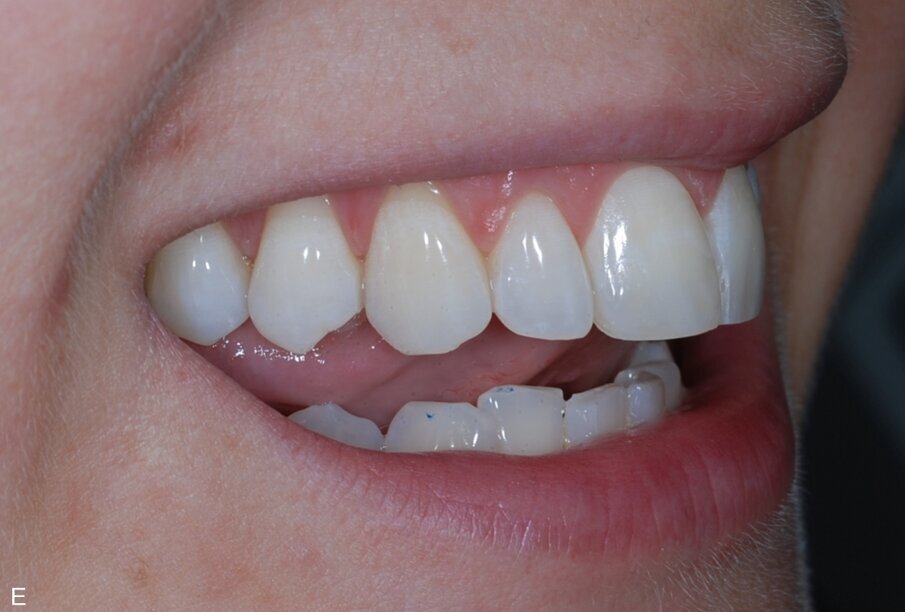

Fig. 3: Pre treatment left lateral

Fig. 17: Post treatment left lateral